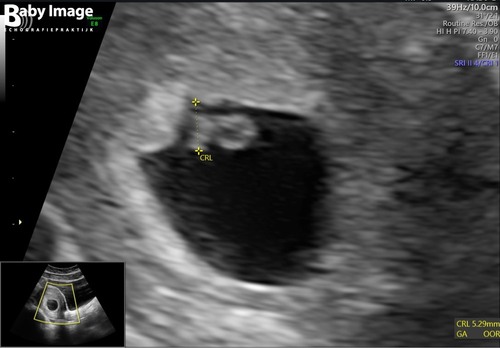

Wij hebben een kloppend hartje gezien ! Was wel met 7 weken maar vanaf 6.3 heb je meestal een mooie echo

Dit was 6 weken dus zie je t verschil hihi